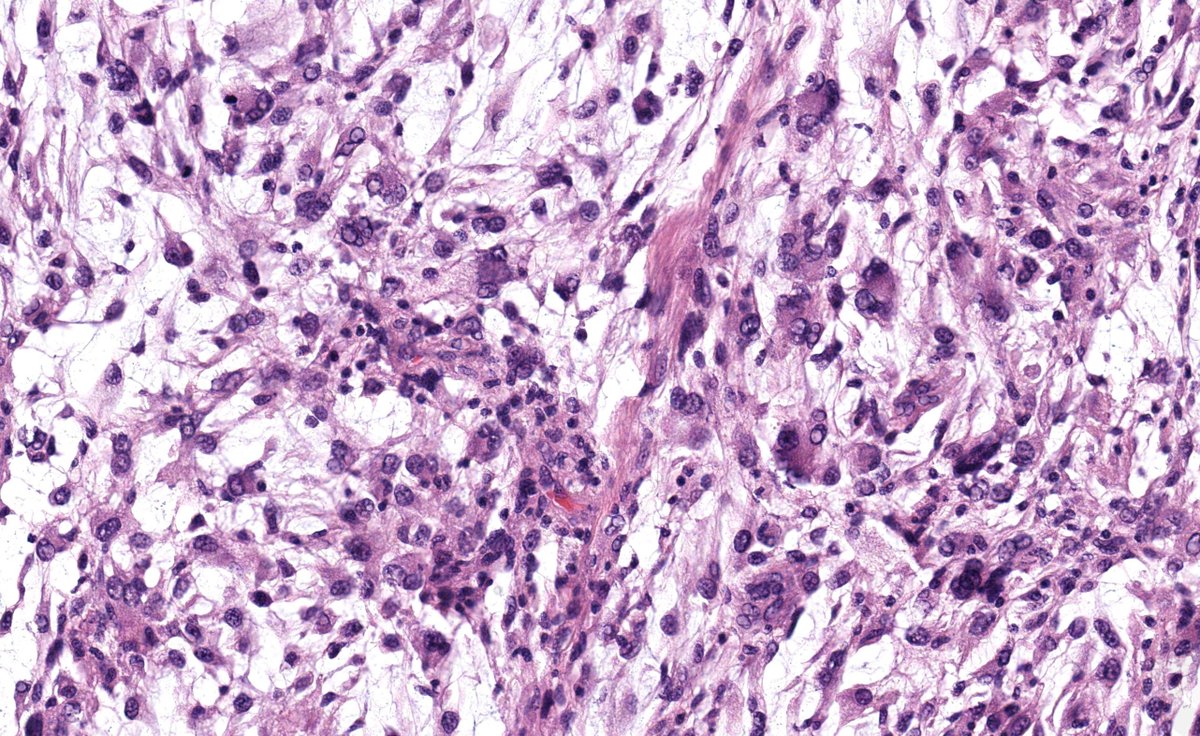

Man with rectal lesion, whats the likely diagnosis here? #GIpath